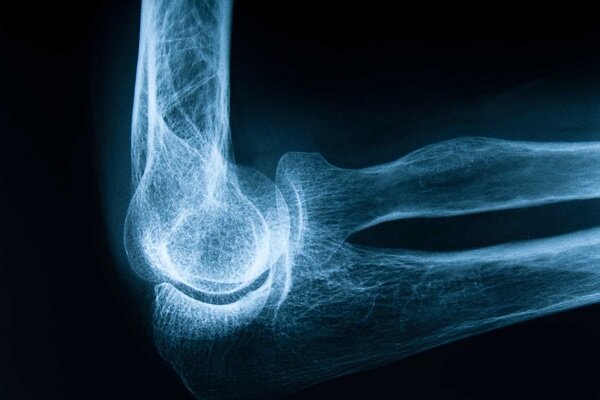

فرح اسماعیلی در گفت وگو با خبرنگار ایمنا درباره اهمیت پیشگیری از پوکی استخوان و راه های ساده و موثر برای حفظ سلامت استخوان ها اظهار کرد: پوکی استخوان بی صدا پیشرفت می کند و ممکن است فرد تا زمانی که شکستگی رخ ندهد متوجه آن نشود، اما زمانی که با یک ضربه ساده یا حتی عطسه استخوان شکسته شود، افراد متوجه می شوند که تراکم استخوان به شدت کاهش یافته است.

وی با اشاره به بار مالی و روانی پوکی استخوان و تاکید بر ضرورت پیشگیری، تشخیص و درمان به موقع این بیماری، گفت: شکستگی های ناشی از پوکی استخوان به ویژه در ناحیه لگن یا ستون فقرات می تواند منجر به جراحی های سنگین، بستری شدن طولانی مدت، محدودیت حرکتی و حتی افسردگی در سالمندان شود و این آسیب ها را نیز نباید صرفاً برای سلامتی به همراه داشته باشد. خانواده ها انجام دادن

وی با تاکید بر نقش دوران کودکی و نوجوانی در شکل گیری تراکم استخوان، تصریح کرد: بیشترین تراکم استخوان در سال های اول زندگی اتفاق می افتد و در صورت عدم تغذیه مناسب و ورزش کافی در این دوران، فرد در بزرگسالی با استخوان های ضعیف تری مواجه می شود.